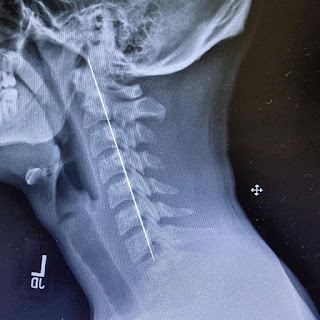

Whiplash Anaheim

Our neck is subjected to various instant and slow movement daily. Whiplash can be the cause of sudden back and forth movement of our neck. But you don’t need to rely on certain expensive medications now. We can provide you the ideal chiropractor for the treatment of whiplash in Anaheim .

Neck Pain Treatment in Orange County

When we are trapped in our daily life schedule, working hard to earn money every day, feed our families, we often tend to forget about our health. We also ignore the fact that our body might be healthy but it is not immortal. This ignorance led to many pain and issues in our body structure. The most common of these is neck pain. Neck pain occurs when we are constantly sitting or standing in a single posture. It can also occur if we are not doing any physical exercises. Normal neck pain treatment options include medications or physiotherapy. For many people, the pain subsides using these options but for others, neck pain may lead to other problems as it does not go away easily. In such a case, you can look for a chiropractor who provides unswerving neck pain treatment in Orange County . Dr. Mina is one such professional who is aiming to change the way we live through is effective chiropractor techniques and treatment options.  Excelling in almost all sorts of hand movements and the ...

Neck Surgeons Anaheim

Dr. Mina is one of the most reputed and reliable neck surgeons in Anaheim . Working day and night to make the lives of patients better, he can help you with treatment options such as soft tissue therapy, motion palpation, manual release technique, physiotherapy, electro-stimulation, and activator.